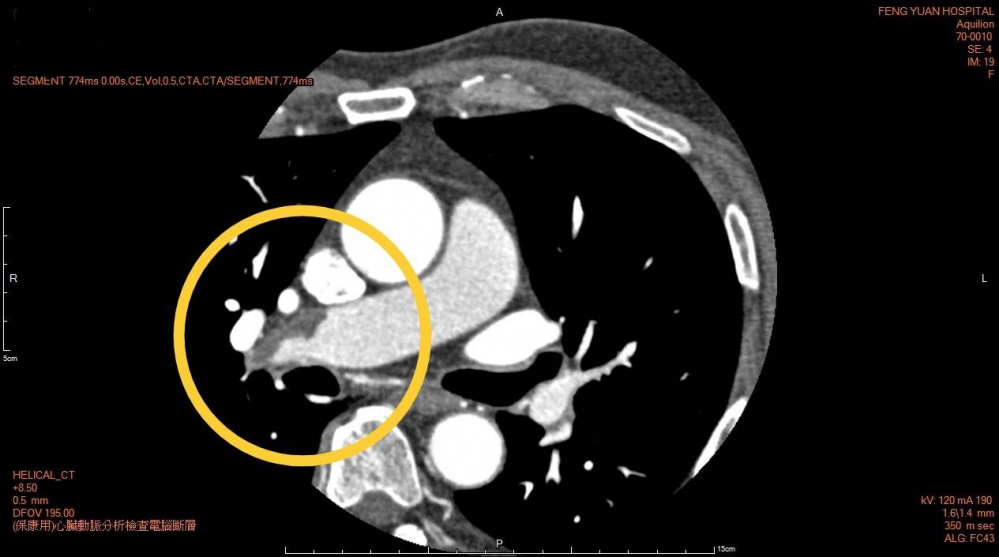

張先生本身是醫師過去也沒有相關慢性病史,此次健檢特別安排心臟冠狀動脈電腦斷層檢查,此檢查是一種非侵入性、相對安全性高的檢查,經由連續而快速與心電圖同步的攝影冠狀動脈的鈣化沈積或動脈硬化斑塊,並進而評估整條的血管阻塞情形,並具有同時檢查心臟周邊如肺臟組織等優點,以達到早期診斷心臟病變的目的。

檢查當天王先生無身體不適且配合檢查,當檢查持續進行放射師也同步檢視影像時,發現異常影像,隨即會同放射科黃竣聖醫師做討論及檢視影像,即發現是不常見的肺栓塞急症,與張先生解釋後立即住院,由心臟科林子翔醫師進行肺動脈心導管檢查治療,化解這個隱形危機,在多科醫療團隊照顧下平安順利出院。

豐原醫院心臟科林子翔醫師提醒民眾肺栓塞是一種由血栓導致的急性疾病,對生命構成嚴重威脅,未必容易察覺,直至開始嚴重時,病徵才會陸續浮現,常見徵狀包括呼吸不順暢、咳嗽、氣喘,以及胸口感到痛楚等,建議民眾如有相關症狀需尋求專業醫師診治,避免遺憾。

豐原醫院放射科黃竣聖醫師也再次強調每個人對於健康檢查的重要性,透過高階影像檢查及早發現潛在的健康危機,對於患有慢性疾病族群更應定期進行全面性的健康評估檢查,在每一次的健康檢查都是早期發現疾病,早期治療的寶貴機會。